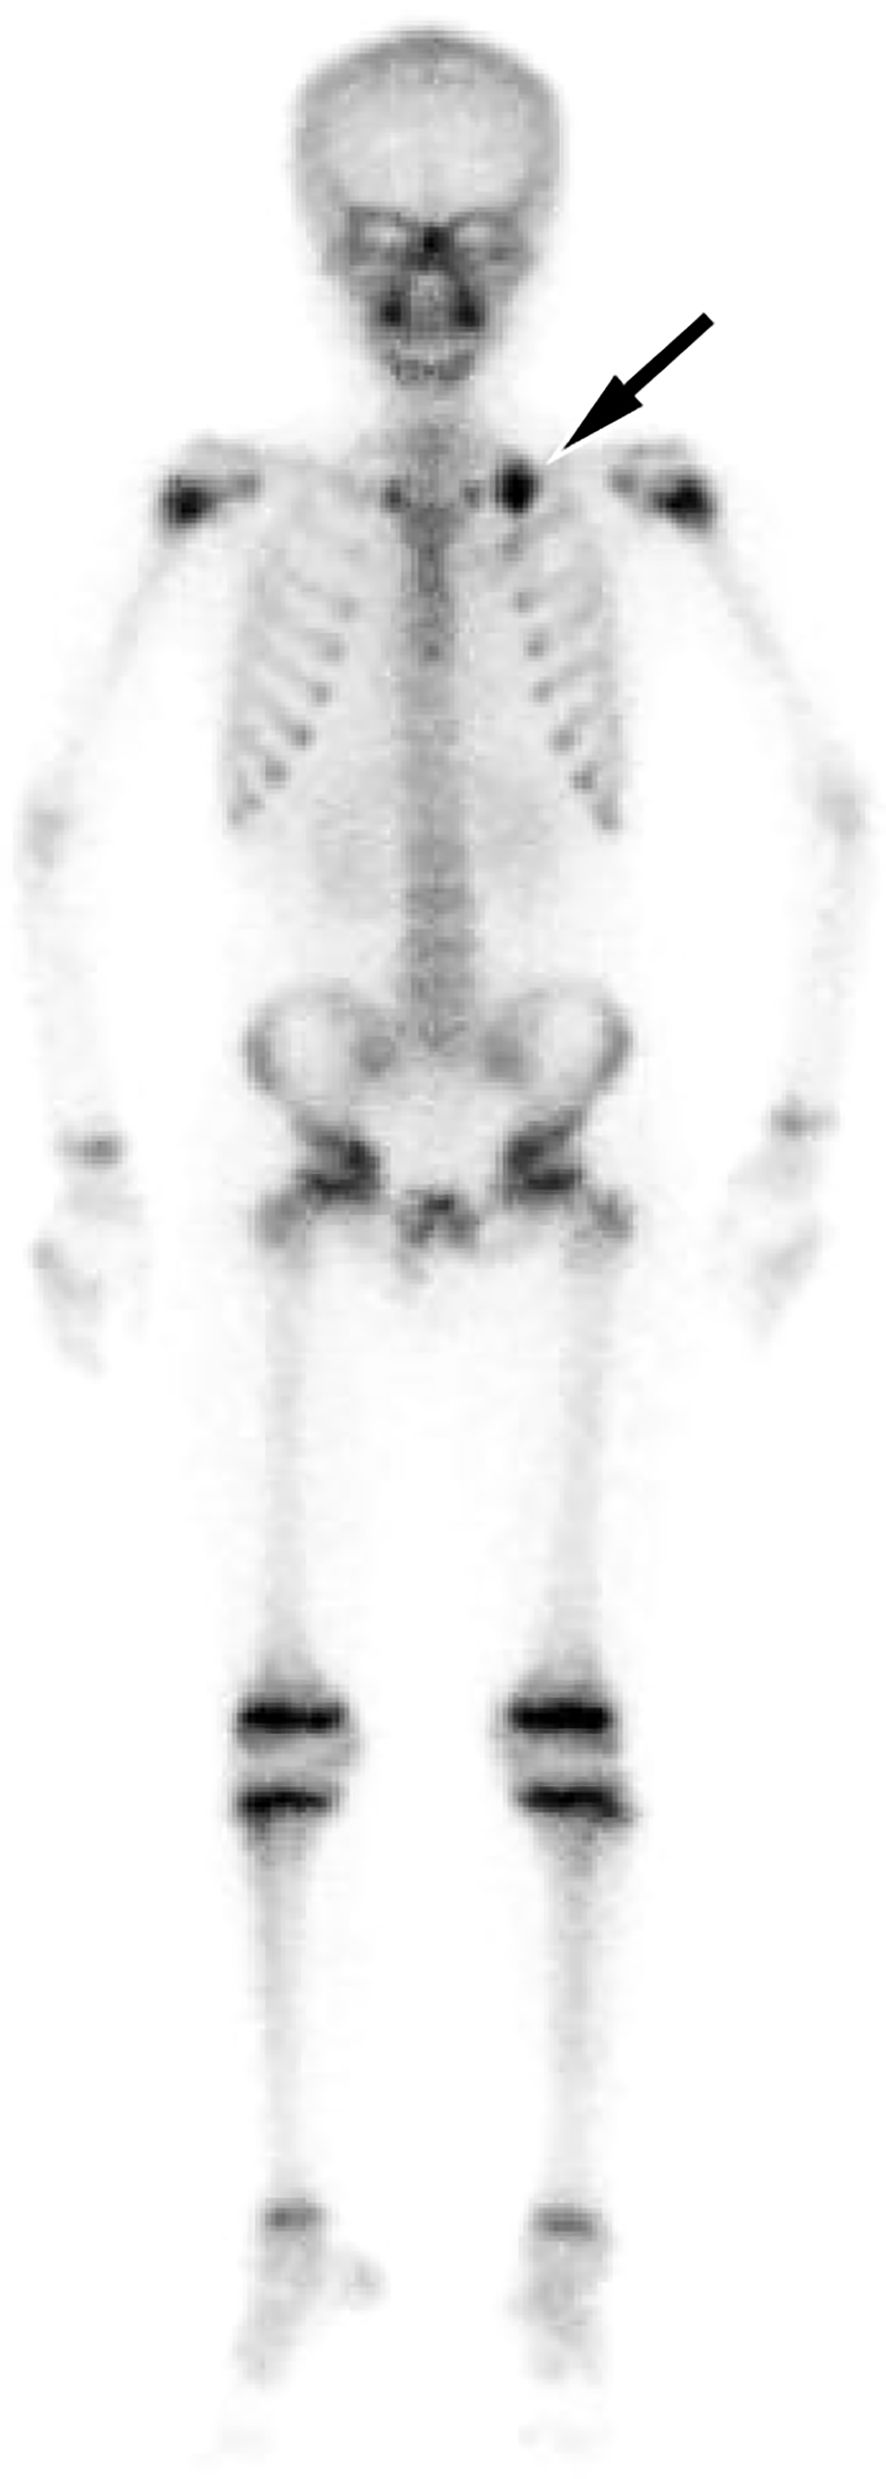

Extraskeletal Ewing sarcoma (EES) is a malignant tumor that arises in soft tissues outside the skeleton. It commonly involves the paravertebral regions, the lower extremities, and the chest wall, with mediastinal involvement being less frequent. Here, we report an 11-year-old male with pathologically confirmed EES occurring in the mediastinum. Chest computed tomography (CT) showed a large soft tissue density mass on his left posterior mediastinum, containing internal low-density cystic necrotic areas. The solid component was isointense to muscle on T1-weighted imaging (T1WI) and mildly hyperintense on T2-weighted imaging (T2WI), whereas the cystic components were hyperintense on T2WI and variably hyperintense on T1WI. On contrast-enhanced CT and T1WI, the mass demonstrated heterogeneous, progressive enhancement, suggesting the possibility of malignant tumor. A needle biopsy confirmed the diagnosis of EES. After diagnosis, the patient received systemic chemotherapy followed by surgical resection of the tumor. We also conducted a systematic review of the published literature on mediastinal EES, summarizing its clinical and imaging features, with the aim of increasing understanding of this rare disease.